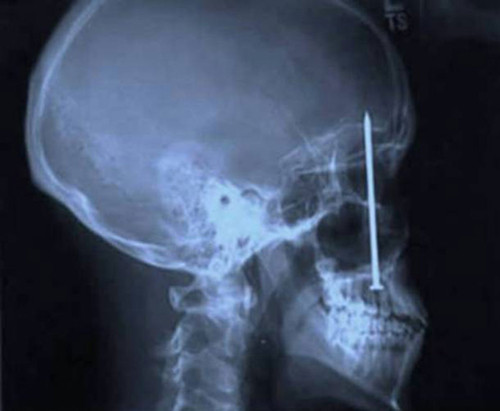

Trong khi đó, bệnh nhân Patrick Lawler lại tìm đến bác sĩ nha khoa bởi cảm giác đau nhức ở răng. Ông vô cùng bất ngờ khi phát hiện chiếc đinh này là nguyên nhân của những cơn đau bất tận.